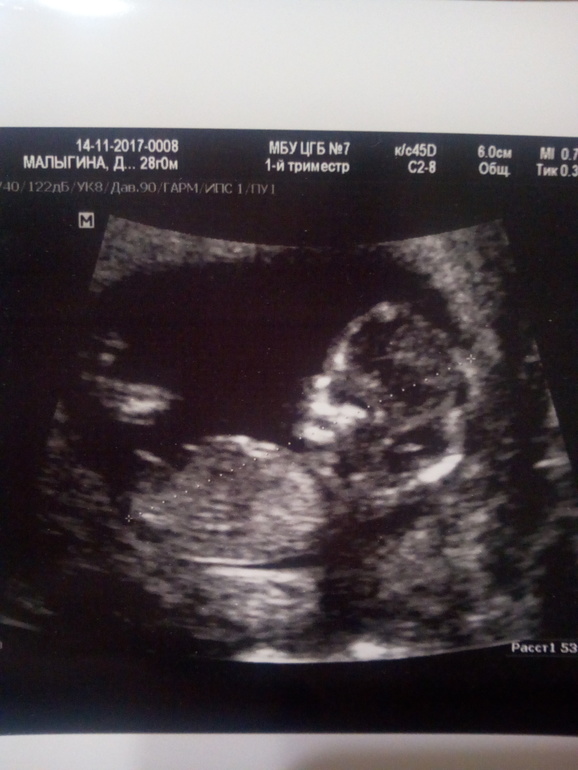

УЗИ, КТГ, доплерСрок на момент узи 12,1. Узист сказала, что девочка) Сейчас смотрюв на бугорок и точно скорее всего девочка))))))

По углу наклона если смотерть, относительно позвоночника, то мальчиковый, по длине вродь на девчачий немного смахивает.

Ага...мне тоже почти все девочки написали , что девочка по половому бугорку....а мне кажется, что парень

Извините, что вклиниваюсь....поглядите у нас половой бугорок...мальчик?

Вроде тоже длиный,но у автора ещё и выше смотрит, мне показалось, что у неё мальчик